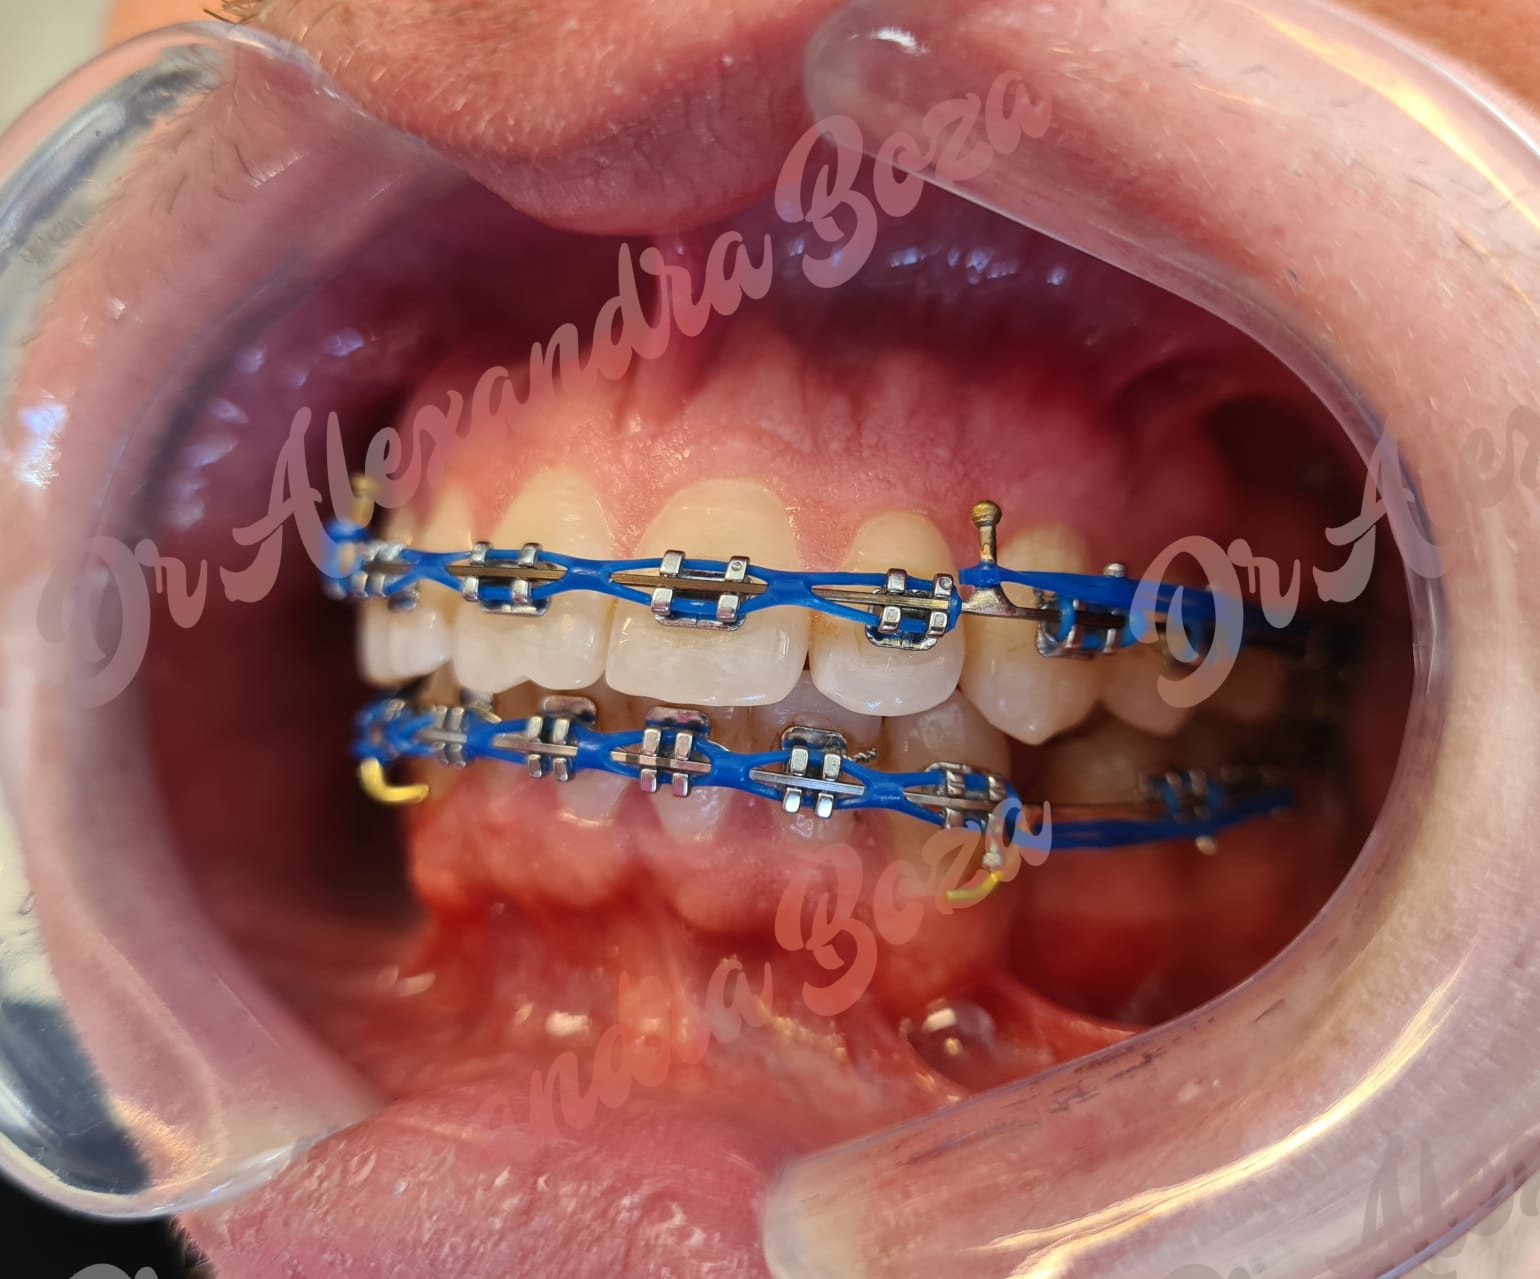

Aparate dentare clasice

Sunt aparatele dentare conventionale si cele mai des utilizate, designul actual facand purtarea lor foarte confortabila. Componentele principale ale aparatului dentar fix in general, si prin urmare, a celui metalic este reprezentat de bracket-uri, elementele care se vor lipi pe dinti si de arcuri care reprezinta elementele ce ajuta la deplasarea (indreptarea) dintilor. Aceste elemente sunt realizate din oteluri de inalta calitate si manufacturate cu ajutorul tehnologiilor de ultima generatie.

Aparate Autoliganturante Metalice

Tratamentul cu bracketii autoligaturanti este mult mai rapid pentru ca sunt mult mai usor de controlat de catre medicul ortodont, actionand in permanenta asupra dintilor. Bracketii autoligaturanti permit ajustari mai rapide si confortabile. Sunt compatibili cu orice tip de tratament ortodontic, la orice varsta, rezolvand majoritatea anomaliilor dento-maxilare.